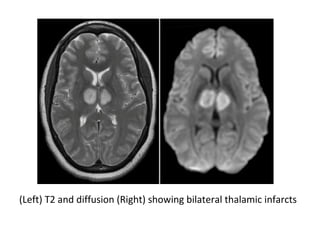

(Left) T2 and diffusion (Right) showing bilateral thalamic infarcts